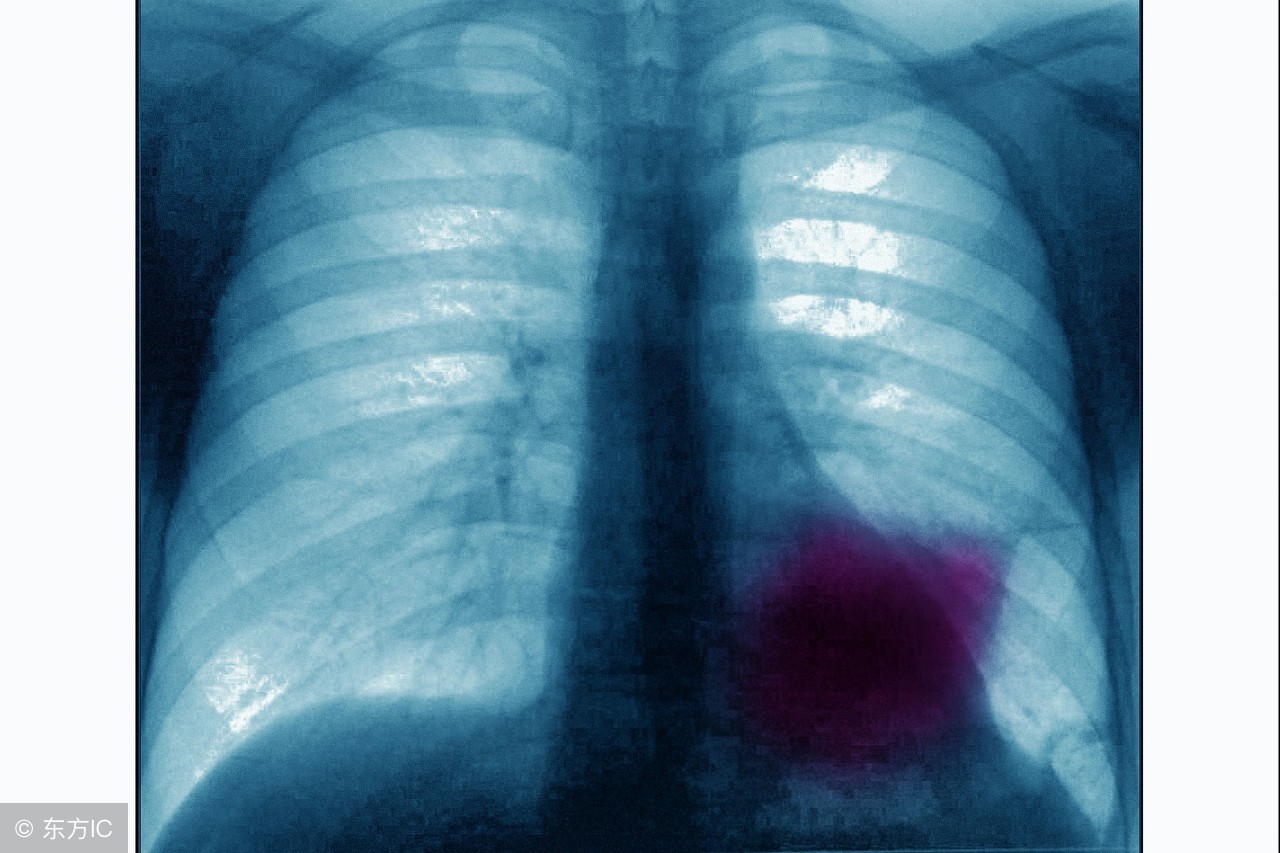

吸烟在生活中似乎成为一种常态,但是临床发现很多肺癌患者都有多年的吸烟史。肺癌给人们带来的危害极大,若是治疗不及时或是选择不适宜的治疗方法,都有可能会形成并发症,那肺癌常见并发症是什么?通过下面的介绍我们来了解一下。